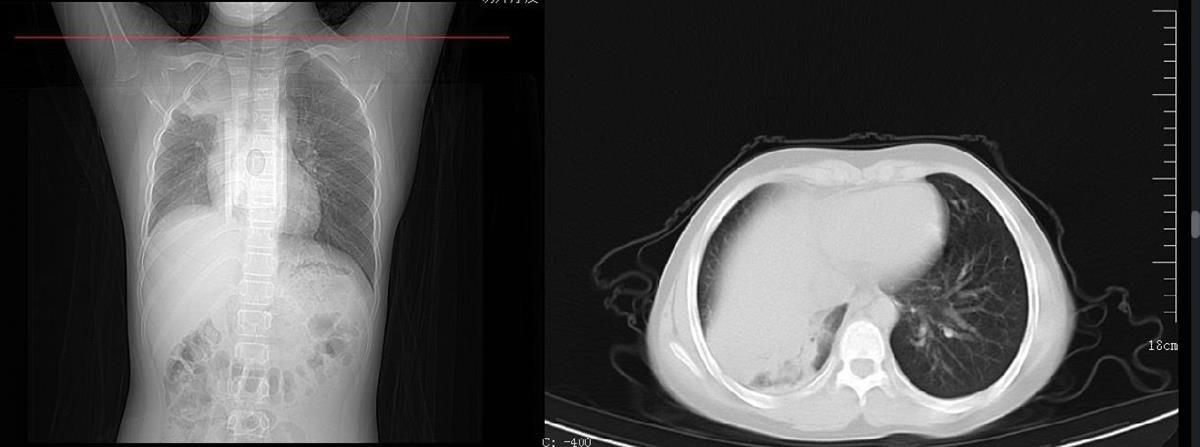

12岁的周周一个星期前出现阵发性咳嗽并伴有发热,家长害怕去医院会交叉感染,于是在家自行吃药治疗。退热之后,周周咳嗽的症状没有好转,甚至开始咳后呕吐,活动后出现胸闷的情况,家长这才将他送往湖北省中医院(湖北中医药大学附属医院)儿科就诊。接诊的儿科主任张雪荣经过一系列的查体后初步判断周周已经发展成肺炎了,“收治入院后查胸片显示,孩子右肺内见片状软组织样高密度影,右肺野内亦可见片状高密度影,考虑右肺部分不张伴胸腔积液可能。”看到胸片上患儿的一侧肺部组织大面积变白后,家长既自责又后悔。好在经中西医结合治疗后,周周目前的症状已经明显好转。